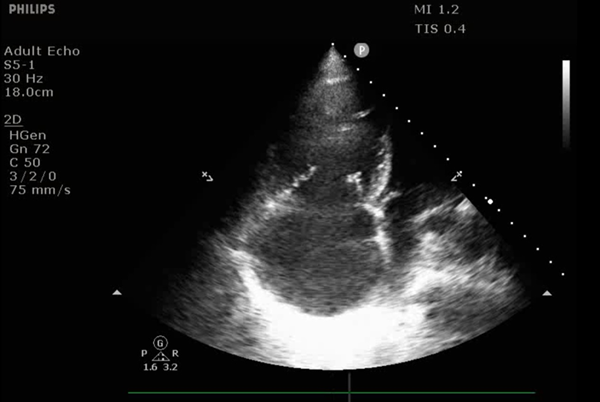

Bedside transthoracic echocardiography shows a dilated right ventricle (RV) , systolic septal flattening, and preserved left ventricular systolic function. His CVP is 20 mmHg, pulmonary artery systolic pressure is elevated, and his mixed venous oxygen saturation has started to fall.